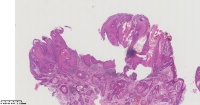

角化棘皮瘤?

性别

男

年龄

45岁

临床诊断

一般病史

面部包块

标本名称

大体所见

图1

倾向脂溢性角化病。